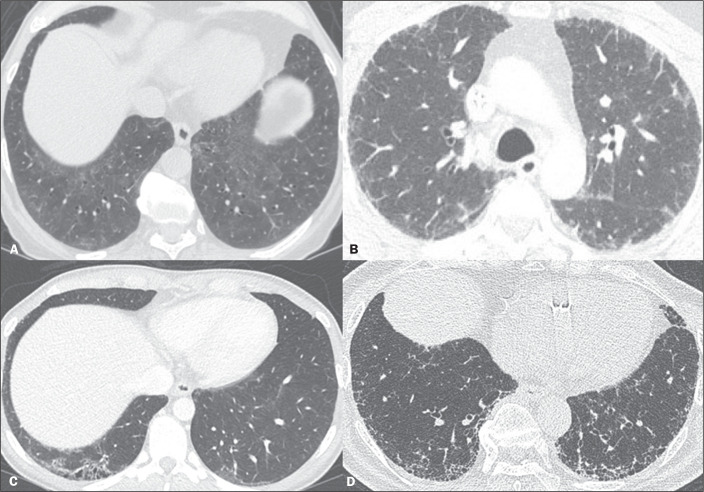

Objective: To conduct a survey on the use of the term "interstitial lung abnormalities" in radiology reports in Brazil, propose an appropriate Portuguese-language translation for the term, and provide a brief review of the literature on the topic.

Results: A total of 163 responses were received, from all regions of Brazil. Although the vast majority (88%) of the respondents stated that they were familiar with the term "interstitial lung abnormalities", there was considerable variation regarding the equivalent term they used in Portuguese.

Conclusion: We suggest that the term "anormalidades pulmonares intersticiais" be used in order to standardize radiology reports and disseminate knowledge of these findings in Brazil.